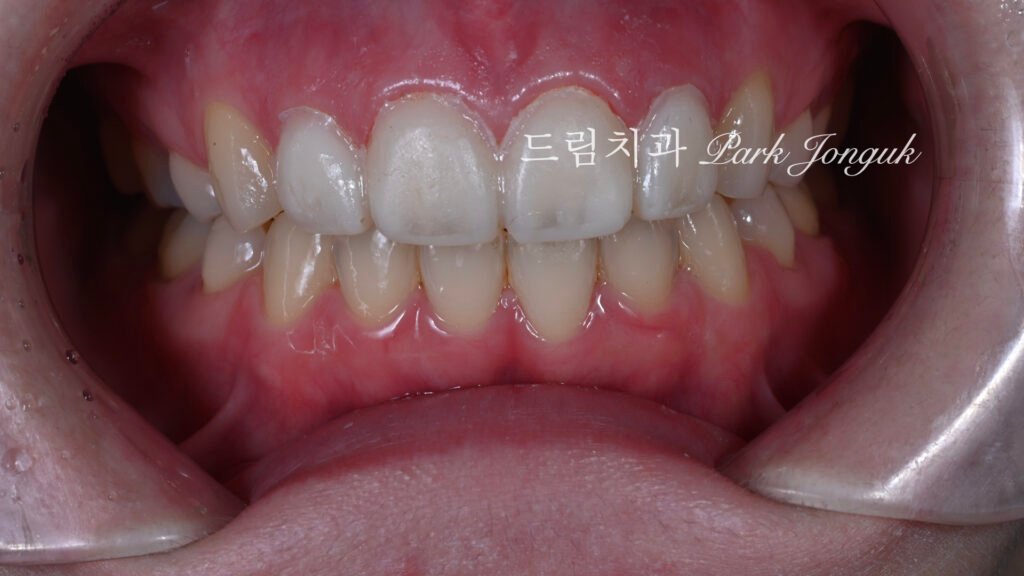

사진 1은 초진 시 구강 내 상태입니다. 여러 문제점이 관찰됩니다.

과대 크기: 치아가 과도하게 크고 투박합니다.

불투명도: 불투명하고 탁한 색조를 보입니다.

평면적 형태: 형태가 단조롭고 평면적입니다.

파절 확인: 일부 라미네이트에 파절이 관찰됩니다.